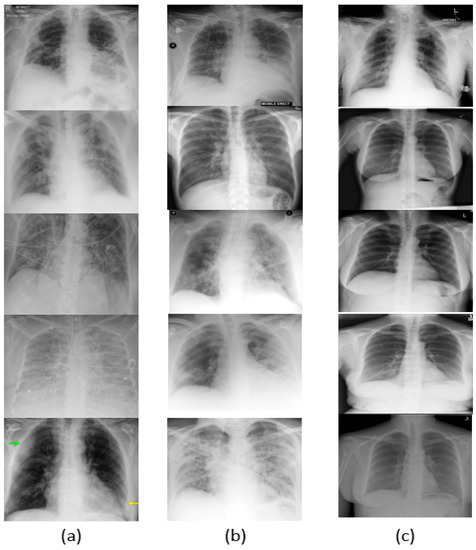

Since COVID-19 is a recent disease, the dataset is still quite limited, and thus data augmentation is needed to obtain more varied samples. For data augmentation, image transformations such as image resizing, random horizontal flipping, random rotation, and color jittering were applied to the input batches. The visual results are shown in Figure 3. As shown in Figure 4a–c, the network was trained over 50 epochs, after which it reached the the maximum accuracy (i.e., overall accuracy) of 95.084 % . Figure 4a,b also show that 50 epochs are sufficient for training. Note that the loss curve plateaus after 50 epochs, and therefore we plot the curves for 50 epochs. The loss curves of the training and validation of the reinitialization phase and classification phase are shown in Figure 4c.

Figure 3. Visual results. (a) Images classified as COVID-19, (b) Images classified as pneumonia, and (c) Images classified as normal.